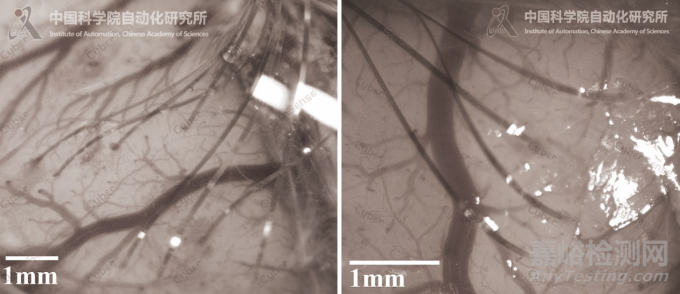

▲動(dòng)物大腦皮層多電極植入效果

CyberSense是“縫紉機(jī)”式柔性電極自動(dòng)植入機(jī)器人,具有多項(xiàng)自主知識(shí)產(chǎn)權(quán),可靈活兼容不同規(guī)格的柔性微電極,應(yīng)用于嚙齒類、非人靈長(zhǎng)類等動(dòng)物的大腦皮層植入。植入機(jī)器人可以在其智能感知系統(tǒng)的引導(dǎo)下,以微米級(jí)的三維操作精度,將多根厚度≤10微米、寬度≤100微米的微絲狀電極植入大腦皮層內(nèi),并靈活地避讓腦血管。由于植入過程是利用一根硬質(zhì)針不斷上下穿梭、操作柔軟的微絲,類似于縫紉機(jī)的工作過程,所以國(guó)內(nèi)外學(xué)者稱其為“縫紉機(jī)”式植入。